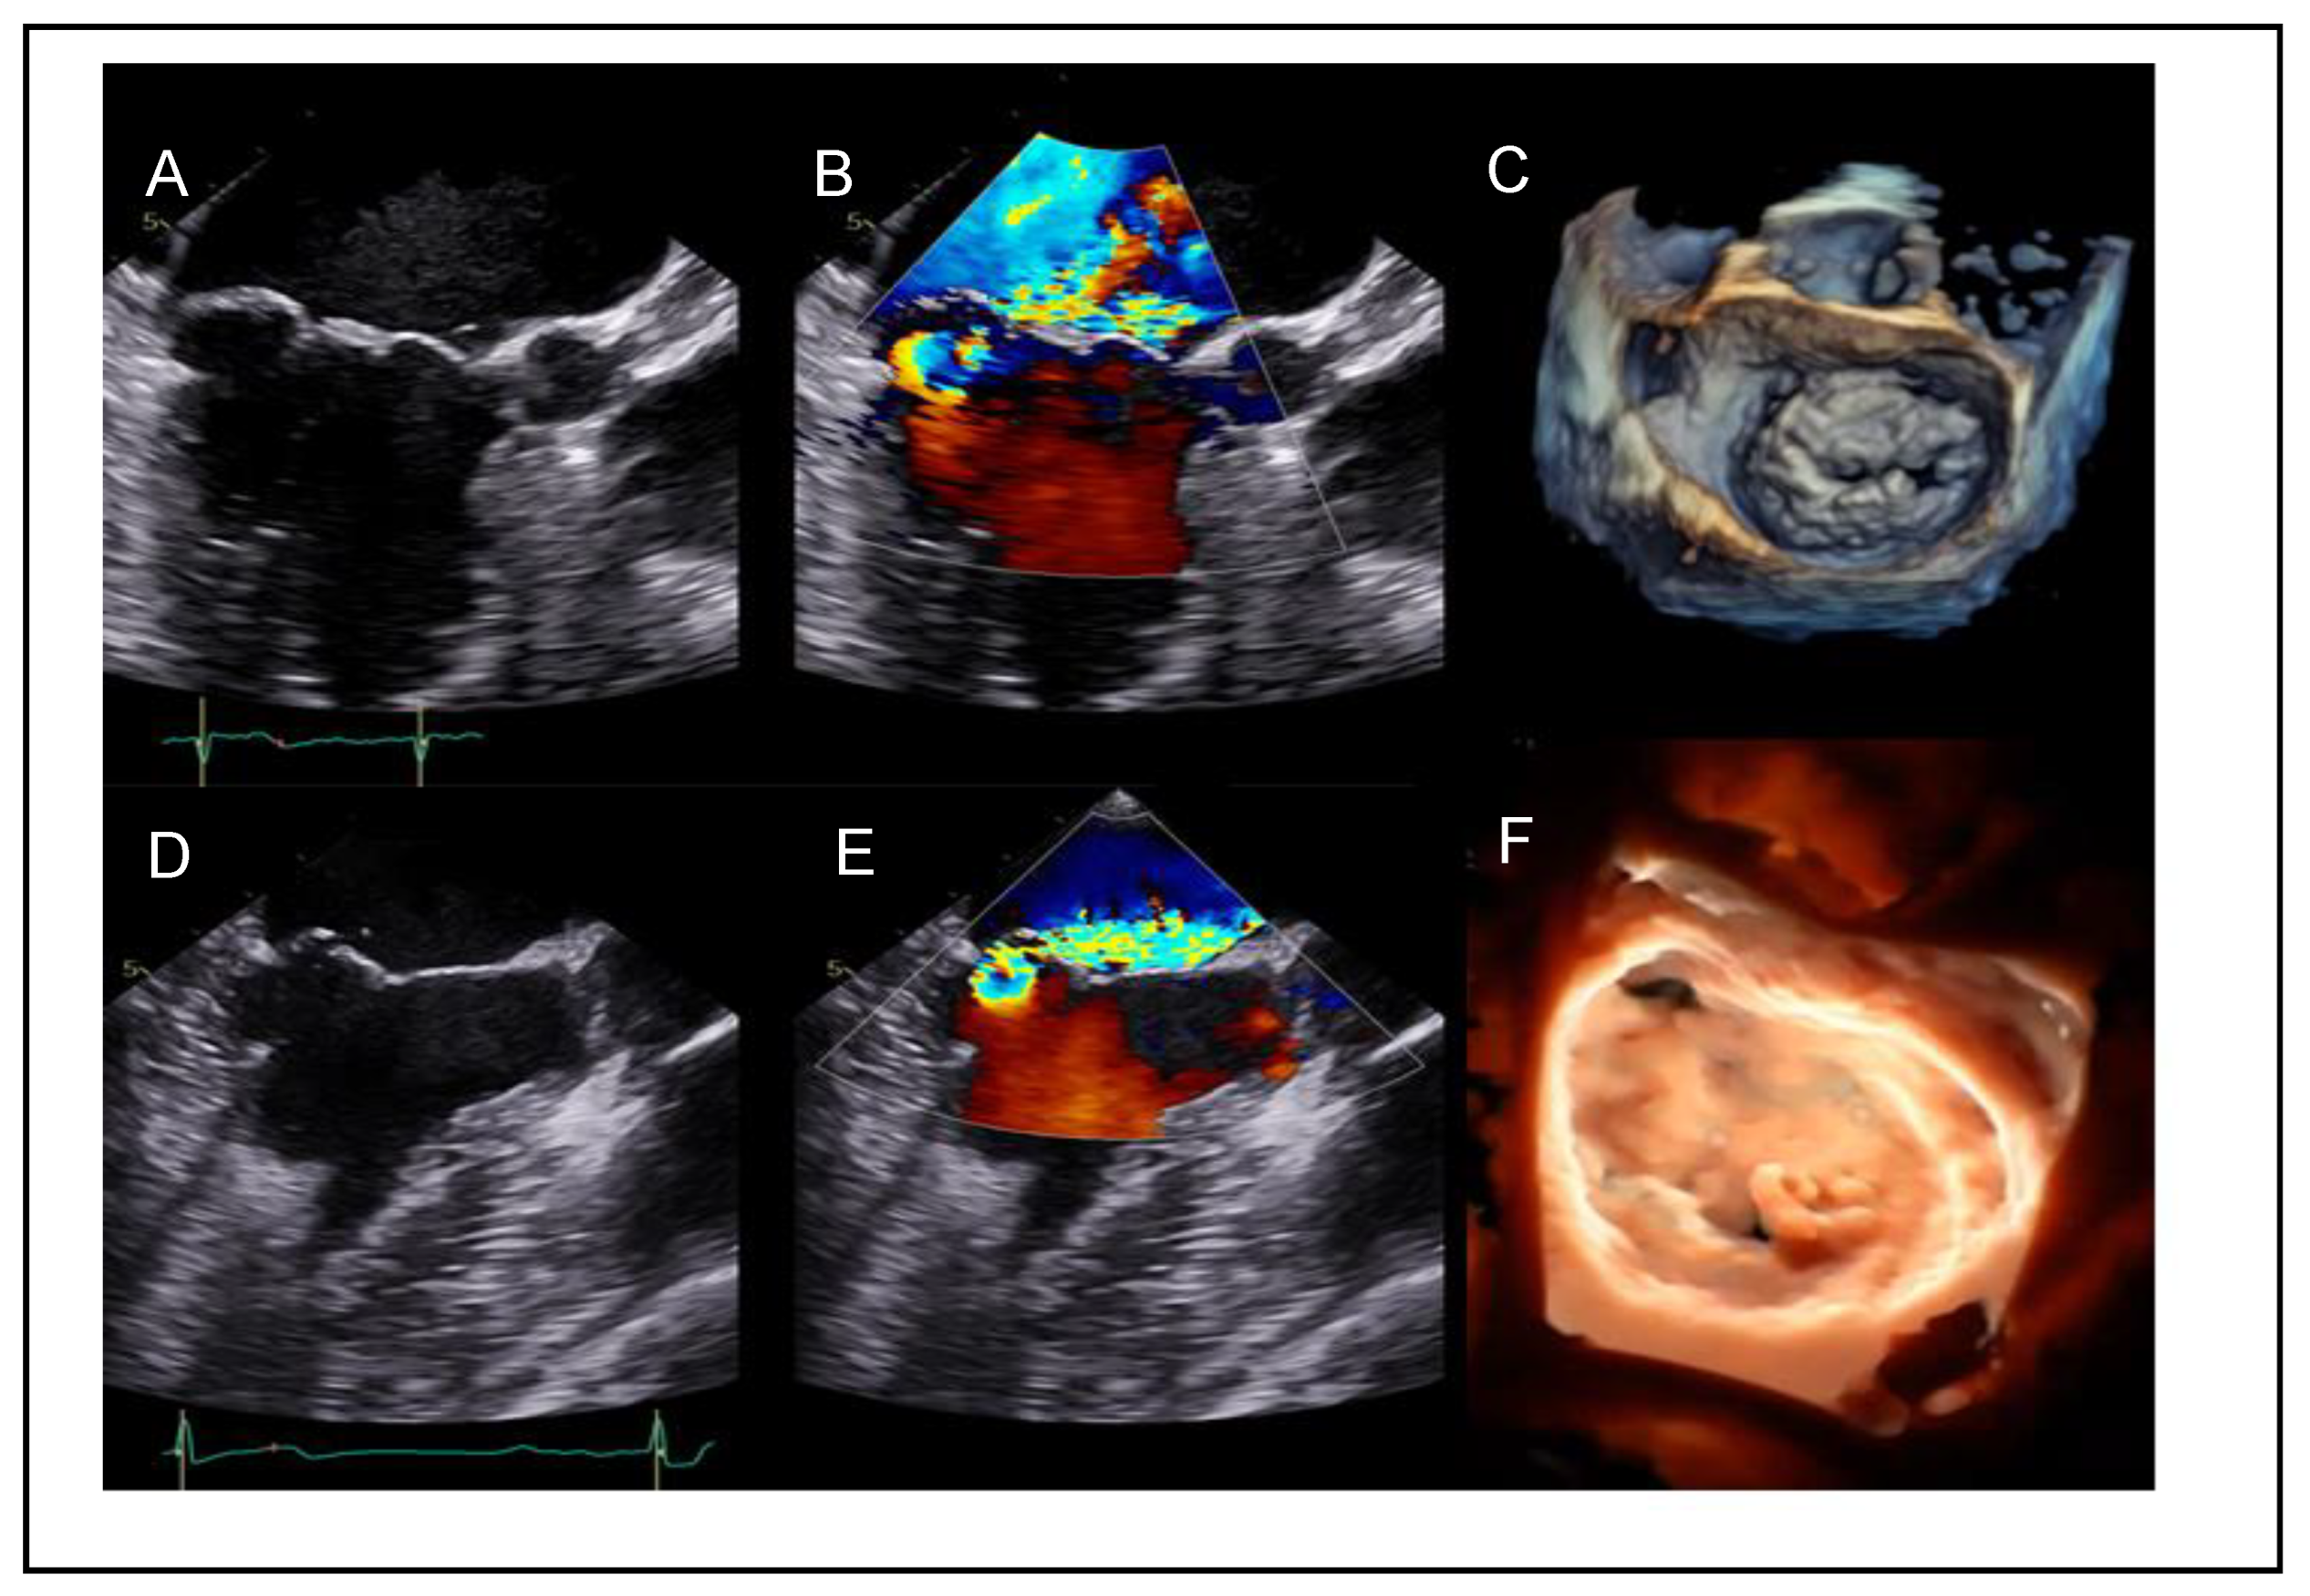

Posterior Leaflet Cleft-like IndentationThe posterior leaflet normally has two indentations that differentiate the scallops. A cleft-like indentation is defined as having a depth of at least 50% of the adjacent scallops [37,38] and 3D imaging is the best option to recognize such abnormalities (Figure 9). This feature makes grasping challenging and may lead to residual mitral regurgitation (MR).